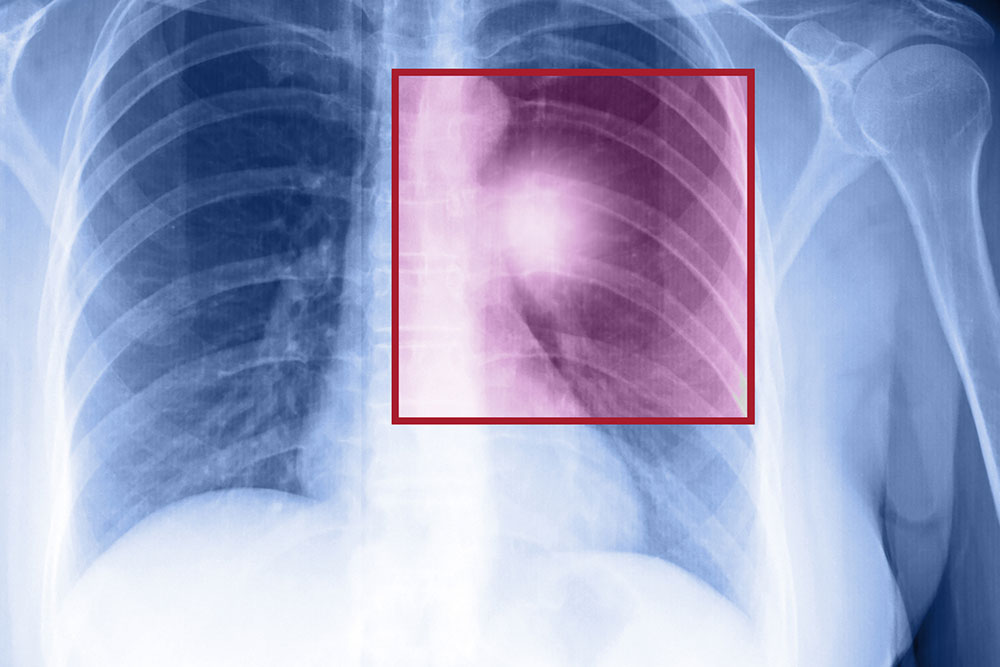

- The presence of tumors in the lung

The best way to treat non-small cell lung cancer is through surgery. Surgery can work if the patient only has a small tumor in the lungs. The size of the tumor is the basic factor considered before undergoing surgery. The surgeon might have to remove the tumor, or sometimes, the entire lung, or a part of it. Sometimes, the surgeon may have to remove the lymph nodes if lung cancer has spread to them.